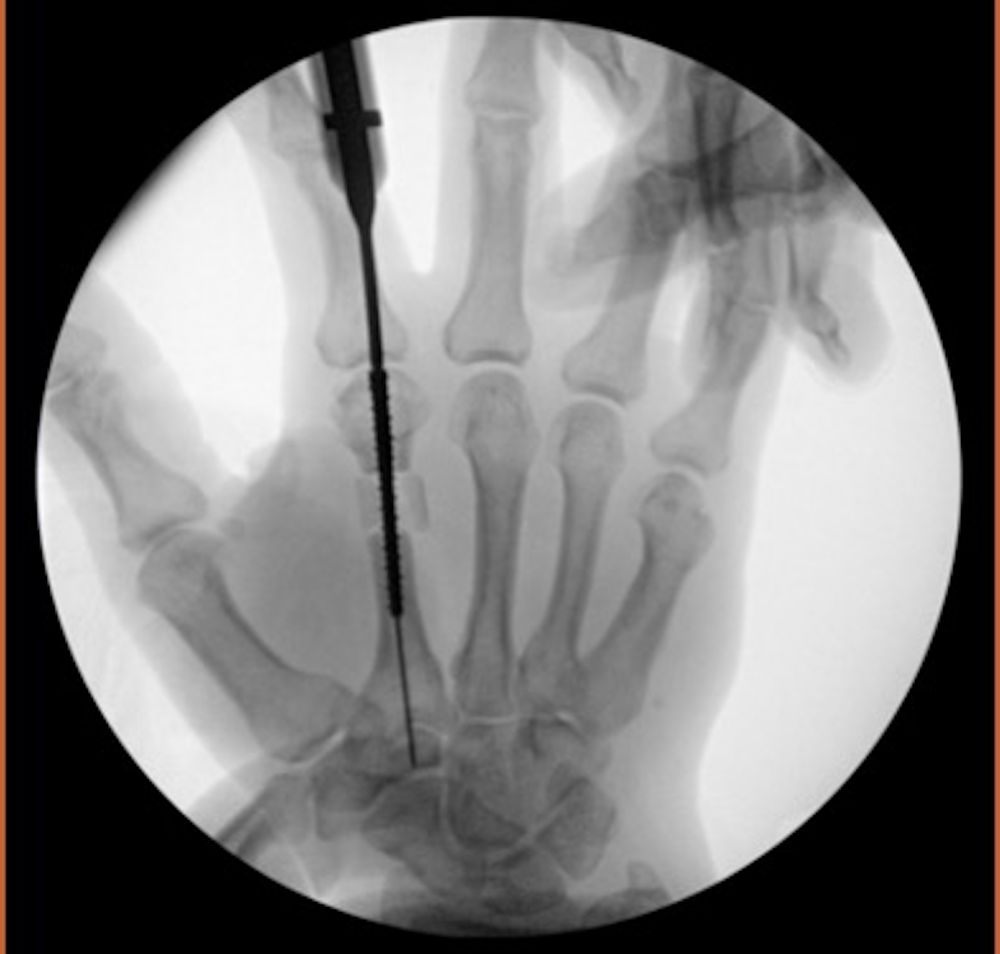

The patient was placed supine with the operative extremity on a hand table. General anesthesia was induced by anesthesia provider. Standard upper extremity tourniquet was applied and surgical preparation utilized for sterile technique. An incision was made on the dorsal hand overlying the index metacarpal. A capsulectomy was then made via a transverse fashion into the metacarpophalangeal joint. An extensor tenolysis was performed of the extensor indicis propius and the extensor digitorum communis to the index finger to aid in range of motion. At that point a volar Bruner incision was made over the palm at the level of the metacarpophalangeal joint. The A1 pulley was released and a transverse capsulectomy was performed. The site for osteotomy was marked at the metacarpal neck-shaft region through the dorsal site and performed with a sagittal saw and an osteotome. Traction was used to distract the metacarpal to the appropriate length in order to reestablish appropriate cascade. The authors prefer to use a Gelpey retractor (Figure 3) to aid in length restoration and assess cascade.

Figure 3. Intraoperative X-ray image of Gelpy retractor holding retraction after index metacarpal osteotomy.